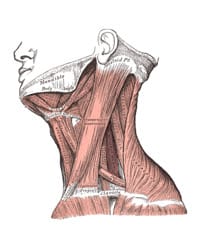

Adson and Coffey at the Mayo Clinic suggest the mechanism by which the anterior scalene muscle causes neurovascular compression in patients with cervical ribs, and are the first to demonstrate that scalenotomy alone can relieve the symptoms of neurovascular compression, without resection of the cervical rib. This procedure becomes popular for several decades, although the recurrence rate is very high. Dr. Alfred Washington Adson created and headed the Section of Neurological Surgery at the Mayo Clinic. He was a pioneer in American surgery, was a founding member and president of the Society of Neurological Surgeons, and was president of the Minnesota State Medical Association and the Minnesota State Board of Medical Examiners.. Dr. Alfred Washington Adson created and headed the Section of Neurological Surgery at the Mayo Clinic. He was a pioneer in American surgery, was a founding member of the Society of Neurological Surgeons, and was president of the Society of Neurological Surgeons, of the Minnesota State Medical Association, and the Minnesota State Board of Medical Examiners. In 1938, Adson performed the first total anterior scalenectomy, removing the entire muscle.

Mr. Thomas Murphy, of Melbourne, Australia, performs the first resection of a normal first rib for the treatment of neurogenic thoracic outlet syndrome. Thomas Murphy described a 28 year-old woman with symptoms of brachial plexus compression. X-rays showed no cervical rib, but Murphy was convinced the brachial plexus was compressed. Murphy performed surgery, finding the broad insertion of the anterior scalene was compressing the brachial plexus. He removed the insertion and a small part of the first rib. The patient had a “perfect and permanent” recovery.

1929

Howard Christian Naffziger and Francis Clark Grant

Naffziger and Grant first introduce the concept of neurovascular compression in the thoracic outlet due to scalene muscle anomalies, without the presence of a cervical rib. They perform the first scalenotomies in patients without cervical ribs, but do not publish their findings until 1937 and 1938. Dr. Howard Christian Naffziger, who trained under eminent surgeons William Halsted and Harvey Cushing, became one of the most esteemed neurosurgeons of his time. He created the division of Neurosurgery and served as Chairman of the Department of Surgery at the University of California San Francisco, was elected president of the American College of Surgeons, and was Chairman of the committee that established the American Board of Neurological Surgeons. Francis Clark Grant trained under eminent neurosurgeons Charles Frazier and Harvey Cushing. Dr. Grant succeeded Dr. Frazier as Professor and Chairman of Neurosurgery at the School of Medicine and the University Hospital at University of Pennsylvania. He published over 200 papers in his lifetime, and refined or developed several neurosurgical procedures and instruments.

Renowned surgeons Alton Ochsner, Mims Gage and Michael DeBakey at LSU publish a comprehensive study of patients with symptoms of neurovascular compression in the thoracic outlet in the absence of a cervical rib, for which they coin the term, “Scalenus Anticus Syndrome”. They credit Naffziger with first recognizing this mechanism in 1929 in patients without cervical ribs, and suggest the term “Naffziger Syndrome”. Dr. Alton Ochsner was named Chairman of Surgery at Tulane Medical School at the young age of 31, and founded the world-famous Ochsner clinic at Charity Hospital in New Orleans, which remains one of the pre-eminent surgical teaching programs in the country. Dr. Ochsner was the first to report the link between cigarette smoking and lung cancer, and he trained some of the most prominent surgeons of the time, including Dr. Michael DeBakey. Dr. Michael DeBakey is one of the most renowned cardiovascular surgeons in the world. After volunteering for military service in World War II, Dr. DeBakey created the concept of the Mobile Army Surgical Hospital (M*A*S*H unit) that enjoyed stellar success during the Korean War. Dr. DeBakey was one of the first cardiothoracic surgeons to perform coronary bypass surgery, was the first man to perform carotid endarterectomy, and made numerous other contributions to and innovations in cardiovascular surgery, including work on the Dacron artificial graft, the heart-lung machine, and the artificial heart.

1938

Alfred Washington Adson

Adson performs the first scalenectomy, or resection of the entire anterior scalene muscle. This procedure is then performed intermittently over the next several decades, until Sanders introduces a more refined technique in 1979.

Richard Sanders

Dr. Richard Sanders introduces supraclavicular scalenectomy in patients with recurrent symptoms following first rib resection for post-traumatic TOS. Due to the great success of this approach, Sanders subsequently utilizes scalenectomy as a primary approach in patients with TOS due to neck trauma.

Scalenus anticus syndrome

Naffziger syndrome

’Scalenus anticus’ is another name for the anterior scalene muscle. Adson and Coffey wrote a landmark paper in 1927 describing their approach of detaching the scalenus anticus from its insertion on the first rib in patients with a cervical rib. Ochsner, Gage and DeBakey in 1935 were the first to describe patients with cervical rib syndrome without a cervical rib who had been treated successfully with the same procedure. They first used the term “Scalenus Anticus Syndrome,” but credited their work to Howard Naffziger, and suggested the term “Naffziger Syndrome” as well.